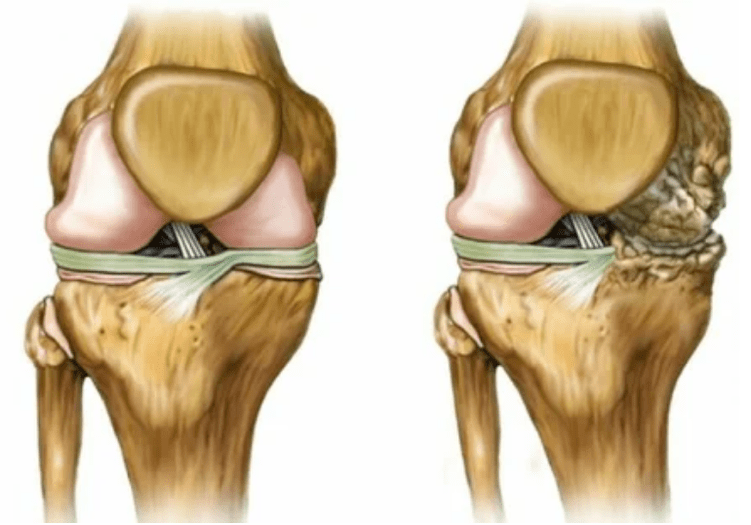

- Kroun wärend Bewegungen - et gehéiert zu der Nonempfänger Manifestatiounen vu Arthosis. Krankheeten ass charge markéiert? Déi eenzeg Gelenefung an enger eenzeger Gelenk (ausser fir Polyhartie), begleet, sech vun engem Onbequemungen, a limitéierten Aktiounen, a limitéierten Aktiounen. D'Natur vun der aktueller ass Wave-ähnlech - am Ufank hunn et sech selwer gesäichen, graduell intensivéiert, awer op 3 Etappen verschwannen;

- Schwellung mat Rötung. Et gëtt lokal no bei der kranker Gelenk lokaliséiert, dëst beweist en entzündleche Prozess an d'Progressioun vun der Krankheet. Den Dokter versteet datt déi synovial Shell betraff ass, dëst provozanzt d'Akkumulatioun vu Flëssegkeet a verstäerkte Péng;

limb Deformatiounen. Erschéngt an enger vernoléisseger Form vun der Krankheet, beweist déi komplett Zerstéierung vum Knorpel an der Erscheinung vun Osteophyten. An dësem Graf ass dann op eng Glidderen op enger Erhéijung vun där Krounung betrëfft, déi de ganze Glibbum beaflosse kann.